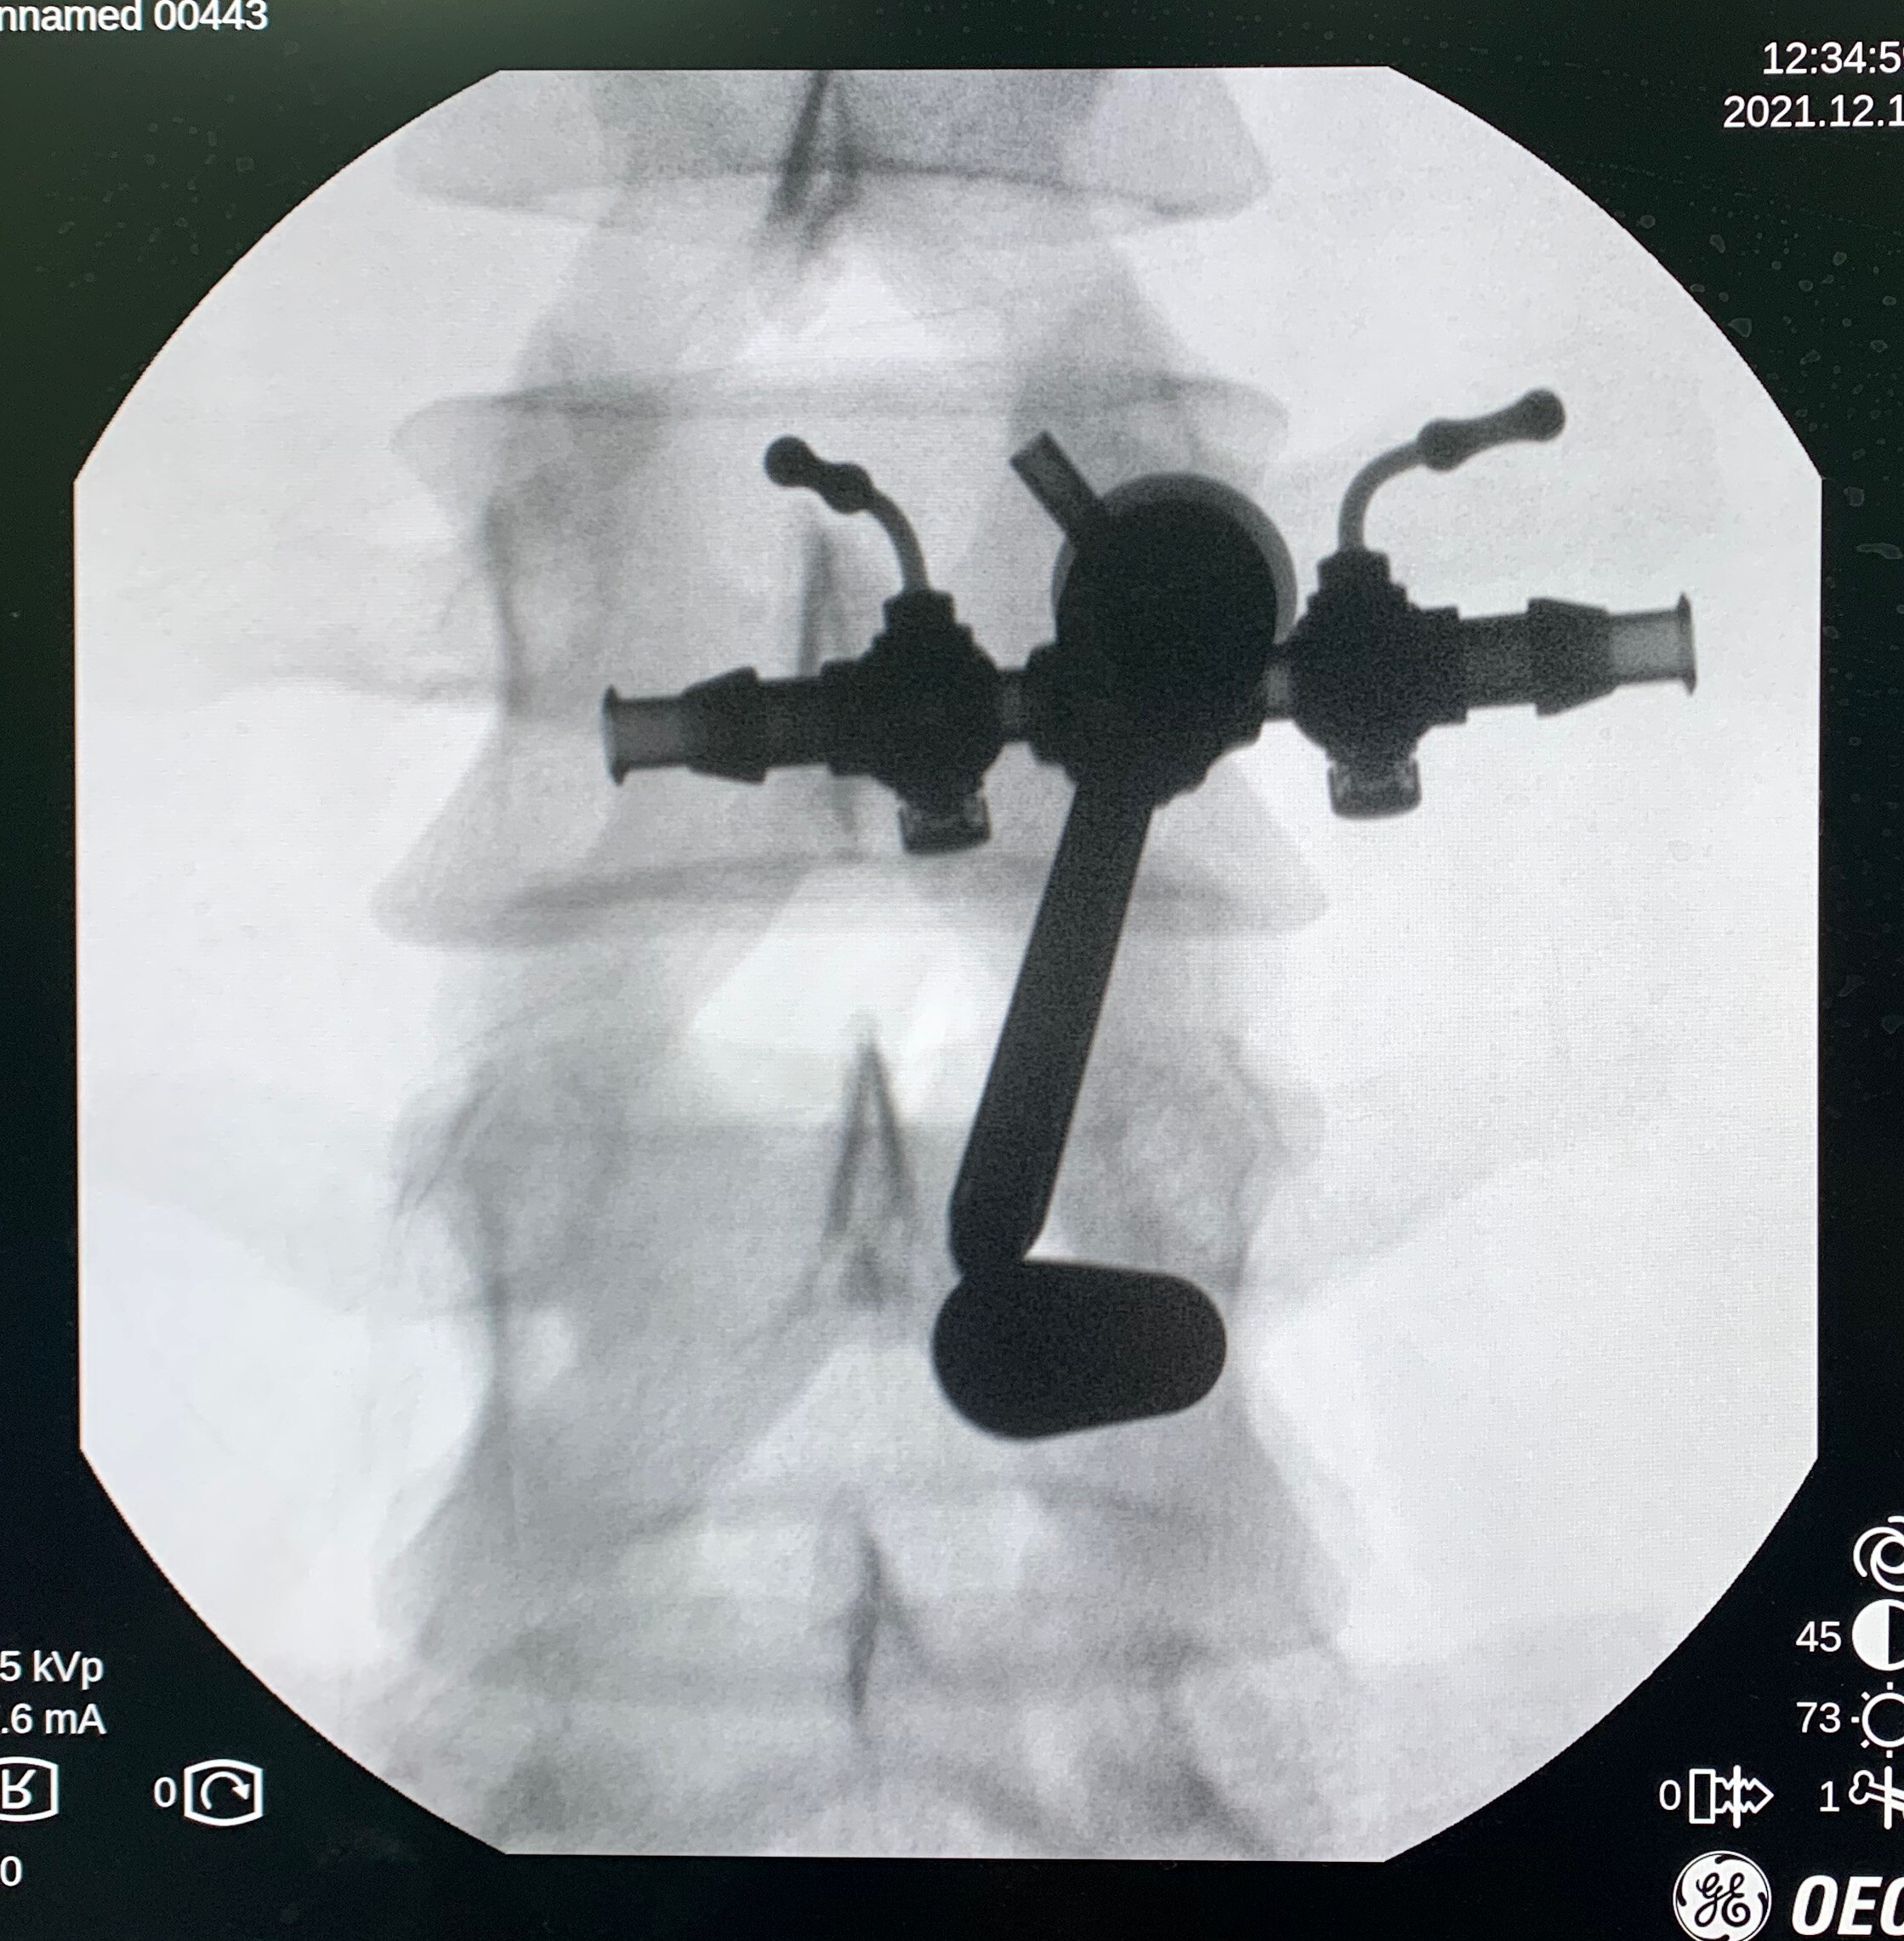

UBE技术即单侧双通道内镜技术(Unilateral Biportal Endoscopy Technique),适用于颈椎、胸椎、腰椎的退行性病变。与椎间孔镜的单通道不同,该技术通常建立两个通道,一个为观察通道,一个为器械操作通道。在UBE内镜辅助下可完成中央椎管、双侧神经根及侧隐窝狭窄的减压,并可在镜下进行椎间植骨融合的一项技术。

2.应用常规椎间孔镜器械和脊柱开放手术器械;